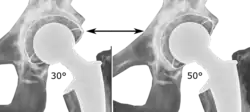

Post-operative projectional radiography is routinely performed to ensure proper configuration of hip prostheses.

The direction of the acetabular cup influences the range of motion of the leg, and also affects the risk of dislocation.[20] For this purpose, the acetabular inclination and the acetabular anteversion are measurements of cup angulation in the coronal plane and the sagittal plane, respectively.

Acetabular anteversion.[105] This parameter is calculated on a lateral radiograph as the angle between the transverse plane and a line going through the (anterior and posterior) margins of the acetabular cup.[105]

Center of rotation: The horizontal center of rotation is calculated as the distance between the acetabular teardrop and the center of the head (or caput) of the prosthesis and/or the native femoral head on the contralateral side.[104] The vertical center of rotation instead uses the transischial line for reference.[104] The parameter should be equal on both sides.[104]